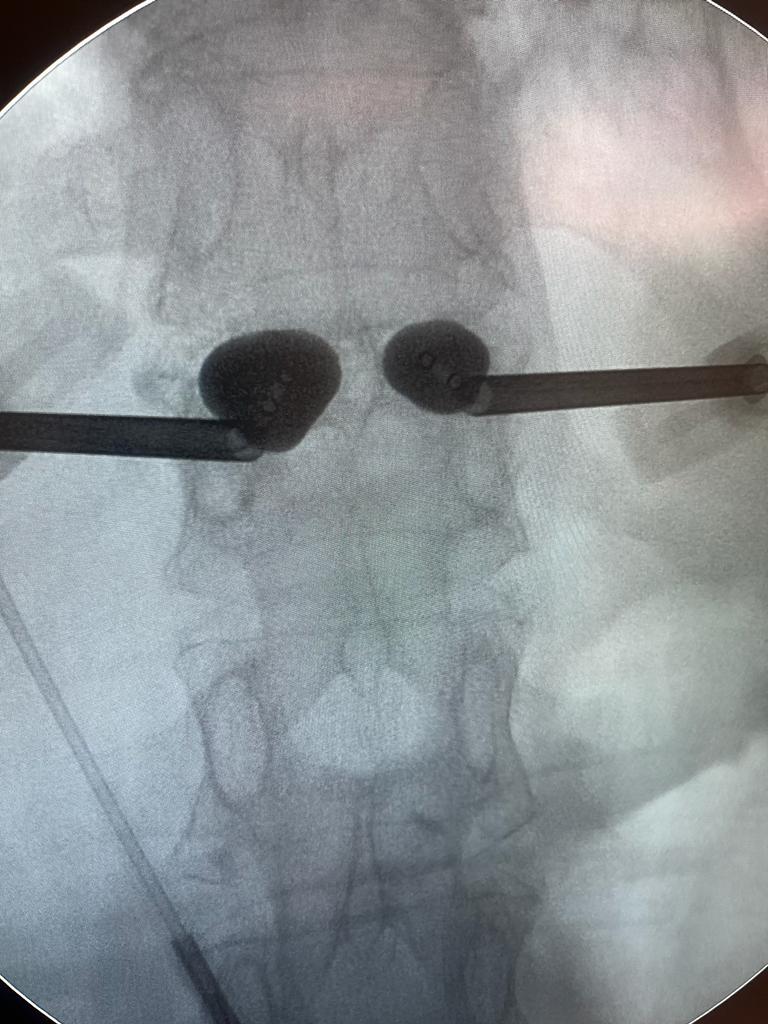

La cementación vertebral es un tratamiento contra el dolor, que consiste en introducir de manera percutánea cemento dentro de una vértebra fracturada, a través de una cánula. Previamente se intenta la corrección de la deformidad vertebral mediante el uso de unos balones hinchables.

Es un procedimiento mínimamente invasivo, se realiza en quirófano de forma ambulatoria, generalmente bajo sedación y anestesia local. Se emplean incisiones de menos de 5mm sobre la vértebra . Utilizando un balón que se introduce a través de una cánula, para crear una cavidad dentro de la cual se inyecta el cemento.